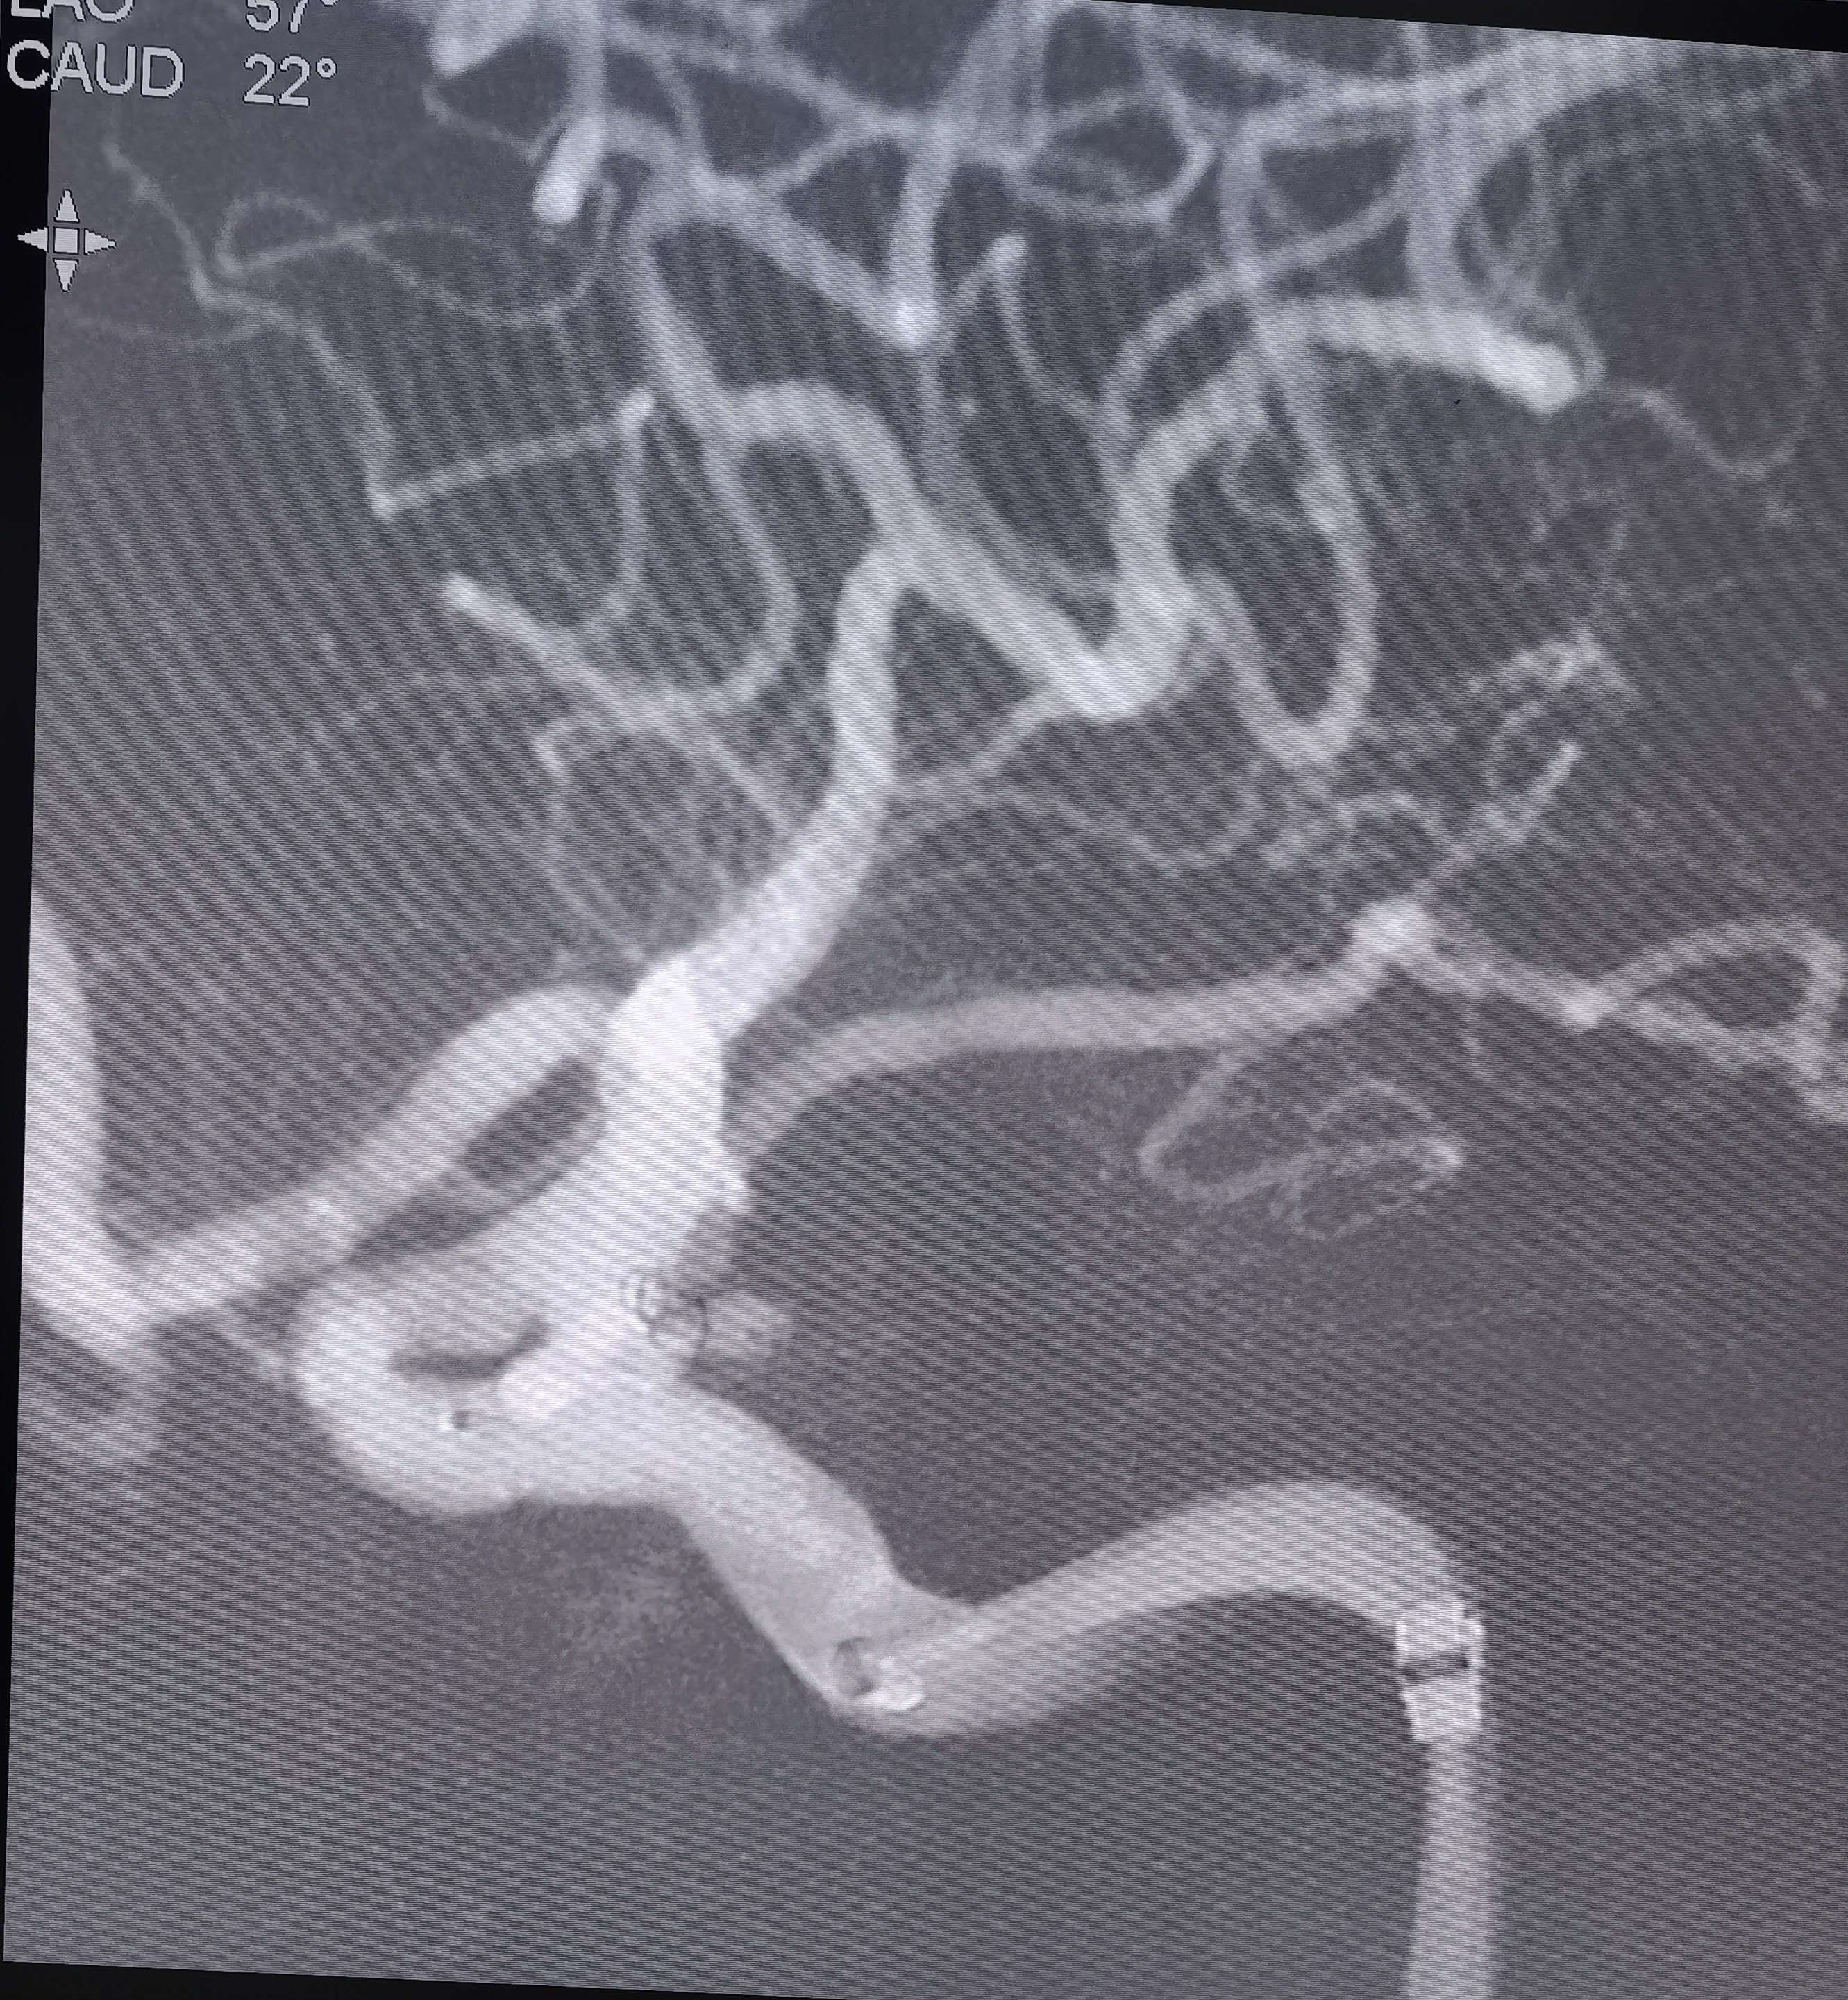

你的浏览器不支持video标签. 入院CT 血管迂曲你的浏览器不支持video标签. RCCA正位,胚胎型大脑后动脉,右侧大脑前动脉纤细。你的浏览器不支持video标签. RCCA3D造影你的浏览器不支持video标签. 右侧3D 右侧后交通动脉瘤形状亦不规则,拟二期治疗。你的浏览器不支持video标签. LCCA正位,胚胎型大脑后动脉,左侧A1供应双侧大脑前动脉。你的浏览器不支持video标签. LCCA3D造影你的浏览器不支持video标签. 左侧3D你的浏览器不支持video标签. 左椎正位,PICA以远未显影。 左侧后交通动脉瘤形状不规则,见子瘤。 拟支架辅助栓塞左侧后交通动脉瘤。 工作位路图,显示子瘤。 微导管首先超选子瘤填塞弹簧圈后,弹簧圈从子瘤脱出,遂应用支架于颈内动脉交通段释放辅助栓塞。你的浏览器不支持video标签. 术中造影你的浏览器不支持video标签. 术中造影你的浏览器不支持video标签. 术中造影你的浏览器不支持video标签. 释放支架,术中造影。你的浏览器不支持video标签. 术后造影你的浏览器不支持video标签. 术后正位你的浏览器不支持video标签. 术后侧位